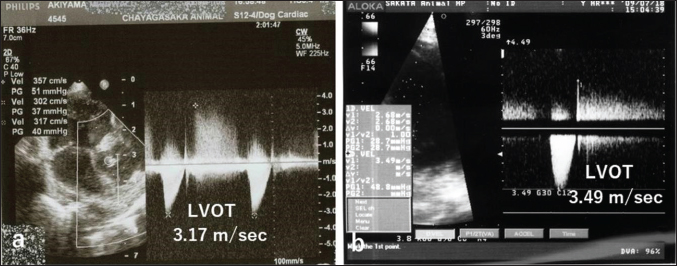

Auscultation revealed a heart rate of 150 beats/minutes and a grade 4/6 systolic murmur in the precordial region near the sternum. Electrocardiography revealed a mean electrical axis of +82º and a mitral P wave in the II, III, and aVF leads. Thoracic radiography showed moderate heart enlargement (vertebral heart score, 10 vertebrae; cardio-thoracic ratio [CTR]: 70%) and increased opacity of the pulmonic field. B-mode echocardiography revealed a small polypoid mass at the dorsal part of the interventricular septum below the aortic valve (Fig. 1a). Two areas of flow acceleration were evident, leading to the mosaic pattern on colour flow Doppler echocardiography: one due to a membranous VSD of 3.17 mm in diameter and the other due to LVOT obstruction caused by the mass (Fig. 1b). In the continuous-wave Doppler (CWD) mode, the LVOT blood flow velocity was 4.55 m/seconds, with a calculated systolic pressure gradient (ΔP) of 83 mmHg between the left ventricle (LV) and aorta (Fig. 2a), and the VSD blood flow velocity was 4.55 m/seconds, with a calculated systolic ΔP of 83 mmHg between the LV and right ventricle (RV) (Fig. 2b). Aortic regurgitation (AR) (Fig. 2a) was also observed. In the CWD mode, the AR blood flow velocity was 3.11 m/seconds, with a calculated diastolic ΔP of 39 of mmHg between the aorta and LV (Fig. 2a).

Fig. 2. CWD echocardiography of the right parasternal long-axis view. (a) The blood flow velocity in the left ventricular outflow tract (LVOT) was 4.55 m/seconds, with a calculated systolic pressure gradient (ΔP) of 83 mmHg between the LV and aorta (AO). The AR blood velocity was 3.11 m/seconds, with a calculated diastolic ΔP of 39 mmHg between the LV and AO. (b) The blood flow velocity in the ventricular septal defect (VSD) was 4.55 m/seconds, with a calculated systolic ΔP of 83 mmHg between the LV and RV. The peak velocity measurement of LVOT, AR, and VSD is not accurate, because of measurements taken using the “beard” instead of the “chin” (see “Study Limitations”).

Fig. 4. CWD echocardiography after surgery. (a) Five days after surgery, the systolic pressure gradient (ΔP) between the LV and aorta (AO) had decreased from 83 mmHg (the preoperative value) to 40 mm Hg. The corresponding values for left ventricular outflow tract (LVOT) velocity were 4.55 and 3.17 m/seconds, respectively. (b) Thereafter, the values were essentially unchanged and were 48.7 mmHg (ΔP) and 3.49 m/seconds (LVOT) at 8.5 months.

The dog was monitored daily with physical examinations, including echocardiography, and the postoperative course was good. However, the dog remained in our hospital for 10 days until discharge to accommodate the owner, who lived remotely. Postoperative auscultation revealed a persistent grade 2/6 systolic murmur, and colour Doppler echocardiography revealed slight residual shunt blood flow through the VSD. As shown via thoracic radiography, the CTR was lower after surgery (66% at 10 days and 65.9% at 8.5 months) than before surgery (70%). As shown via CWD echocardiography, the systolic ΔP between the LV and aorta was also lower after surgery (40 mmHg at 5 days) than before surgery (83 mmHg) (Fig. 4a); after 5 days, it remained essentially unchanged and was 48.7 mmHg at 8.5 months (Fig. 4b). At 8.5 months, the dog had no clinical signs of heart disease and her body weight had increased to 3.9 kg. According to the referral hospital, the dog had no cardiac complications during the next 11 years.

In our study, CWD echocardiography was especially useful for monitoring blood flow velocity by calculating ΔP before and after surgery. As determined using this modality, the systolic ΔP between the LV and aorta was 83 mmHg immediately before surgery. According to the referral hospital, it was 50.7 mmHg 2 months before surgery. This slow increase in the ΔP presumably reflected the slow growth of the tumour, which was likely benign (Han et al., 2012). Five days after surgery, the ΔP had decreased to 40 mmHg (Fig. 4a), with little change over the next 8.5 months (Fig. 4b). Although echocardiography may indicate whether a tumour is benign or malignant, biopsy is required for definitive diagnosis of a cardiac myxoma.

For CWD echocardiography, Kyranis et al. (2018) identified the measurement site for peak velocities on Doppler wave to ensure the exact value is taken at the “chin” and not the “beard”. In this case (Fig. 2a and b), we measured the peak velocities at the beard, not the chin. Therefore, the exact volume appears to be slightly lower. However, this cannot be corrected because of a lack of original image data. On echocardiographic assessment of the LVOT, pulsed-wave Doppler (PWD) is used for LVOT flow evaluation when no flow acceleration is noted to accurately measure the specific velocity at the region of interest. When there is a fixed obstruction or dynamic obstruction (as is possible in this case owing to the mobile mass) leading to flow acceleration, then aliasing of PWD can occur, which forces us to use CWD for evaluation of the peak velocity and peak gradient (Koplitz et al., 2006). However, in our case, we did not obtain PWD data.